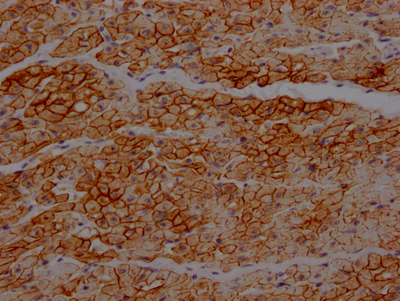

IHC (Immunohistochemistry)

(IHC image diluted at 1:100 and staining in paraffin-embedded human heart tissue performed on a Leica BondTM system. After dewaxing and hydration, antigen retrieval was mediated by high pressure in a citrate buffer (pH 6.0). Section was blocked with 10% normal goat serum 30min at RT. Then primary antibody (1% BSA) was incubated at 4 degree C overnight. The primary is detected by a Goat anti-rabbit IgG polymer labeled by HRP and visualized using 0.05% DAB.)